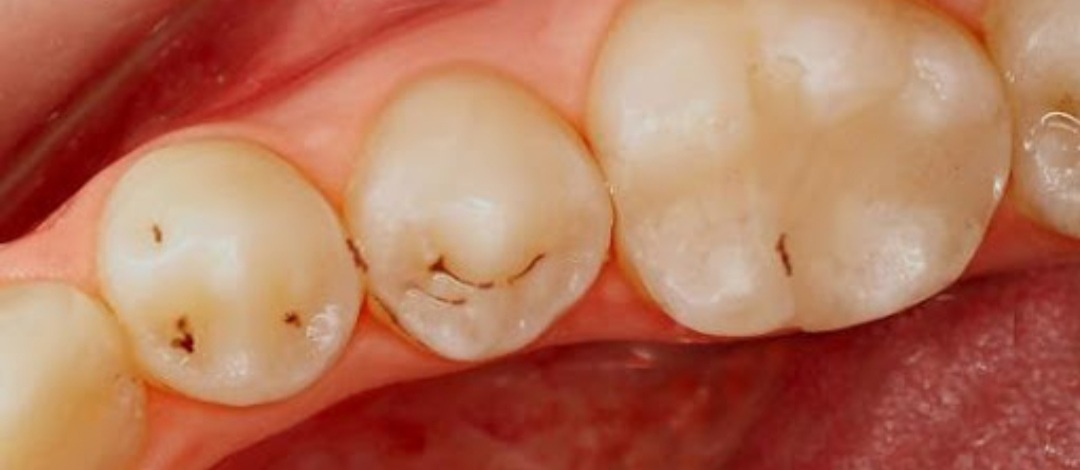

Author: Liss Posted: wo, 07/08/2020 - 17:49 ik heb dit op 4 tanden ,wat is dit Attach Lieneke Een teken dat je goed Een teken dat je goed gepoetst hebt ;) Dit waren ooit beginnende gaatjes en door goed poetsen/eten zijn de gaatjes niet verder je kies ingegaan. Het neemt wel kleurstof op door de veranderde structuur. Geen zorgen dus! Stuur privébericht Login of registreer om te reageren do, 07/09/2020 - 11:45 Permalink 25572 weergaves

Lieneke Een teken dat je goed Een teken dat je goed gepoetst hebt ;) Dit waren ooit beginnende gaatjes en door goed poetsen/eten zijn de gaatjes niet verder je kies ingegaan. Het neemt wel kleurstof op door de veranderde structuur. Geen zorgen dus! Stuur privébericht Login of registreer om te reageren do, 07/09/2020 - 11:45 Permalink